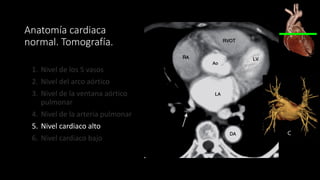

Anatomía cardiaca normal. Tomografía.

1. Nivel de los 5 vasos

2. Nivel del arco aórtico

3. Nivel de la ventana aórtico pulmonar

4. Nivel de la arteria pulmonar

5. Nivel cardiaco alto

6. Nivel cardiaco bajo